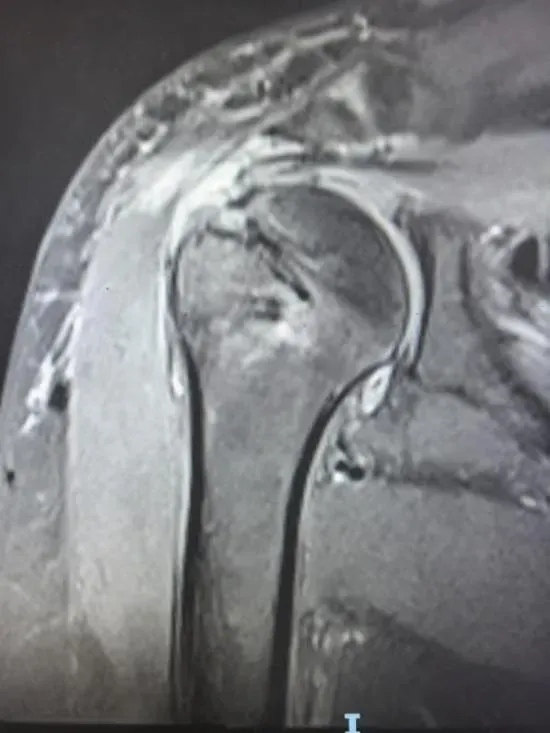

54岁的患者是一名建筑工人,长期的重体力劳动让他的肩关节不堪重负。6个月前,他因“右肩巨大肩袖撕裂”在外地某三甲医院接受“关节镜下肩袖缝合修复术+肱二头肌长头腱固定术”。术后虽完成系统康复,但右肩功能仍未改善:胳膊抬不高,前屈仅60°(正常人能到180°),外展80°(正常人能到180°),后伸连20°都不到;日常生活与工作深受影响,甚至无法完成抬臂、举物等基础动作。今年9月,患者右肩疼痛突然加重,肌力明显下降,连自主穿衣都难以完成。为求进一步治疗,患者慕名前往延安市中医医院运动医学科就诊,经过详细检查,团队明确诊断:右肩肩袖修复术后再撕裂,且冈上肌腱全层撕裂伴回缩、冈下肌腱部分损伤,肩胛下肌还存在严重粘连。

“患者长期干重活,加上术后再撕裂,手术面临巨大挑战。” 运动医学科团队庞军主任介绍,“一是组织质量差:肌腱残端回缩,脂肪大量替代肌肉(GoutallierⅢ级),弹性和修复能力大幅下降,肌腱与骨头的结合处还出现了瘢痕化、骨床硬化;二是解剖结构乱:之前的手术导致肩峰下间隙粘连、关节囊挛缩,原有的固定锚钉还挡住了手术操作空间;三是愈合环境糟:反复损伤让肩关节局部血供不足,细胞活性降低,慢性炎症还影响修复组织生长。”

术前及术中探查所见如上图